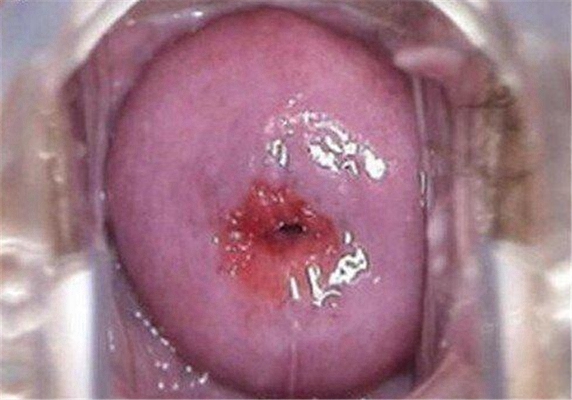

重度宮頸糜爛圖 (24)